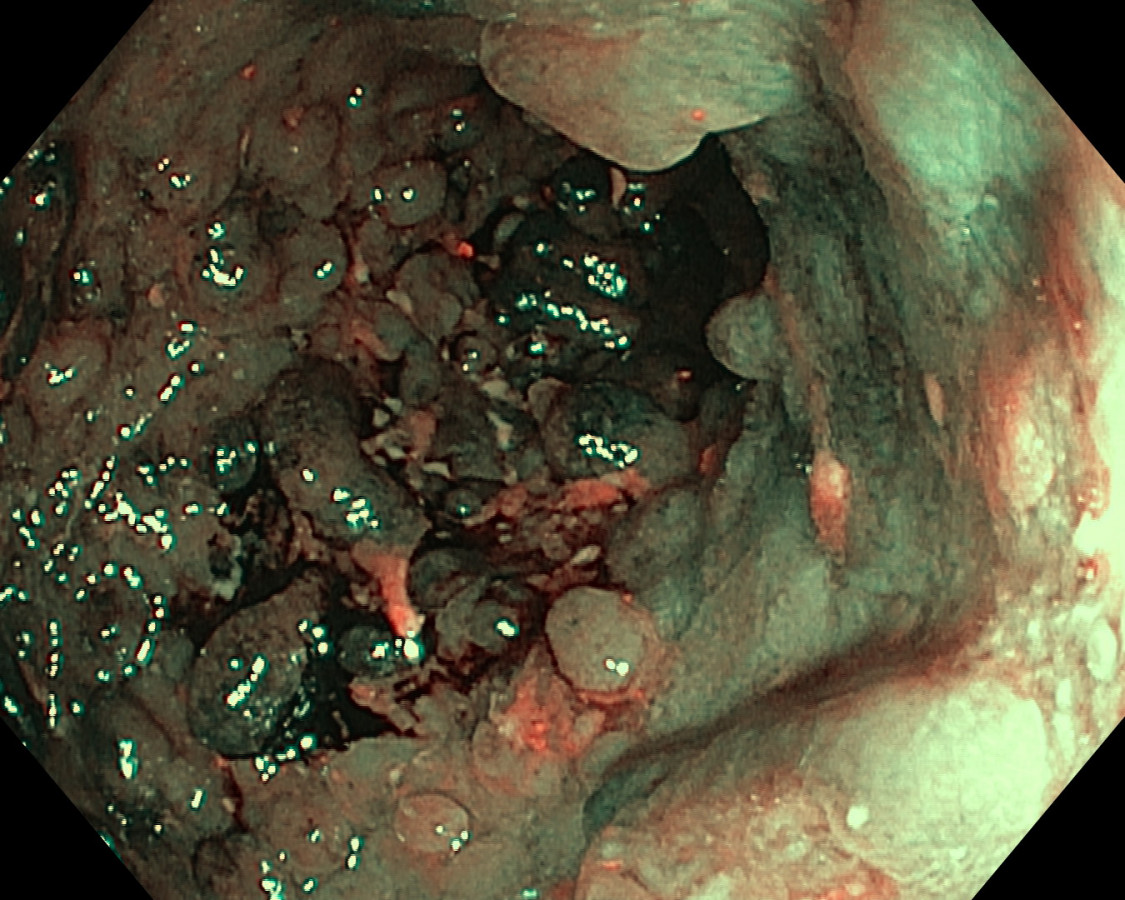

Polypóza u pacienta s ulceróznou kolitídou

Pacient s UC - dg. od r. 2009 ako pankolitída, od 4/2010 pri imunosupres. th. kompletná remisia ochorenia, už vtedy pseudopolypózne štádium, noncompliance, kontrola až pri relapse v r. 2017. Odvtedy +/- chodí na kontroly. 07/2023 relaps, systémové kortikosteroidy, ATB, s efektom - 9/2023 pankolonoskopia - pravostranne nález dobrý, ľavá strana síce bez aktivity ochorenia, aj histolog. remisia, ale polypózne št. hlavne v sigme - foto - dysplázia zachytená nebola. Bude ťažké odsledovať KRCA v tomto teréne. Dalo by sa uvažovať o chirurgickej liečbe ? Ďakujem.

U nemocných s UC je výskyt zánětlivé polypózy, kterou rozumíme přítomnost více než deseti zánětlivých polypů, relativně častý. Je odrazem těžce probíhající zánětu. Zánětlivé polypy nemají sami o sobě potenciál maligní degenerace a v tomto ohledu není potřeba je kontrolovat nebo odstraňovat. Mnohočetné zánětlivé polypy však znesnadňují průběh dispenzárních koloskopických prohlídek, protože významně omezují přehlednost po sliznici a detekci dysplastických změn. Druhý negativní dopad vícečetných zánětlivých polypů je u udržování aktivního zánětu a elevaci hodnot fekálního kalprotektinu. U nemocných s mnohočetnými zánětlivými polypy v rektu a rekto-sigmatu mohou být persistující tenesmy a intermitentní krvácení vyvolány právě jejich přítomností. V těchto případech je endoskopicky odstraňujeme.